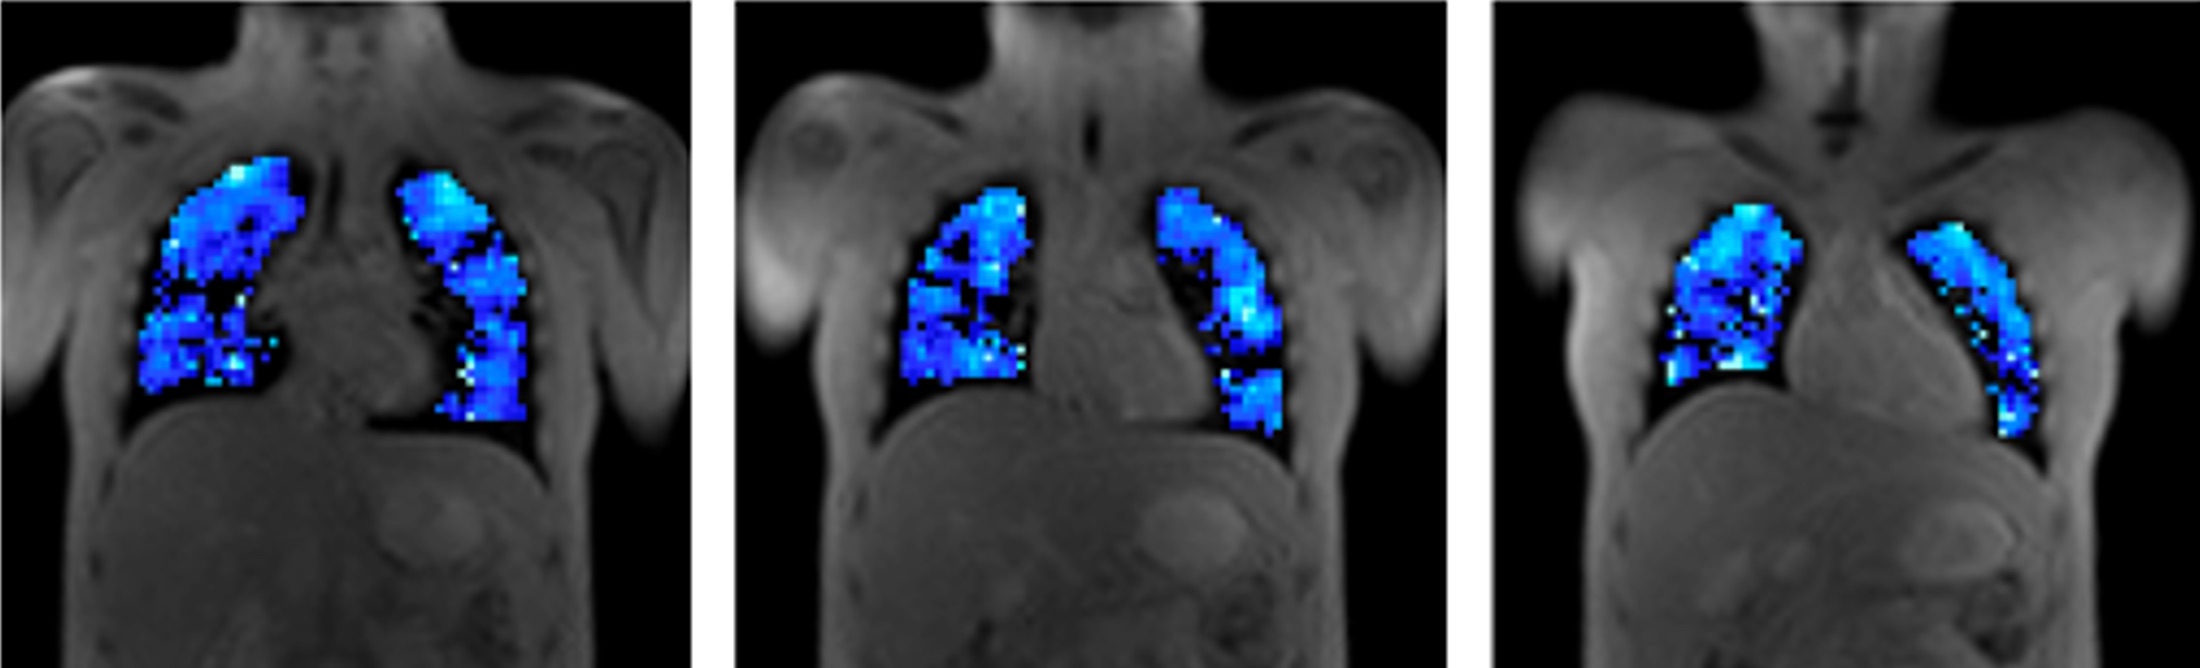

From study design to final reporting, Bioxydyn delivers repeatable MRI biomarkers that reveal tissue function, physiology and change. Our operational excellence and metrology help you compare results across sites, scanners and timepoints.

Disease areas and services supporting quantitative MRI biomarkers across clinical trials.